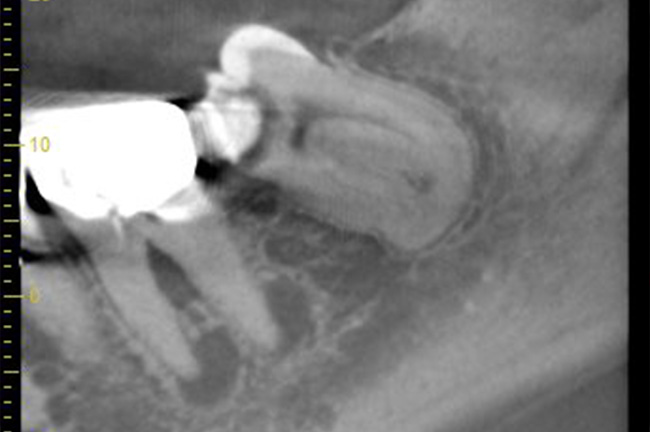

事前にCT撮影を行い神経との位置関係を確認して抜歯を行いました。右下親知らずは歯ぐきの中に完全に埋まり、

また斜めに生えていた為歯ぐきを切って親知らずの頭部分を分割して抜きました。

抜歯前